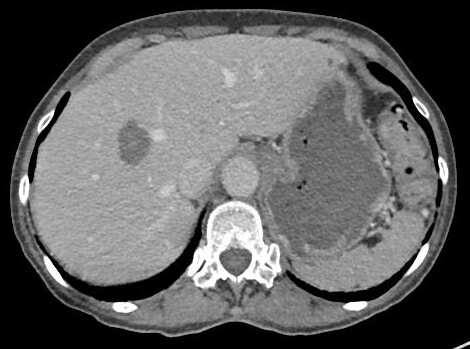

This is a CT image obtained 1 month after microwave ablation demonstrating the lack of enhancement in the treated area in the liver.